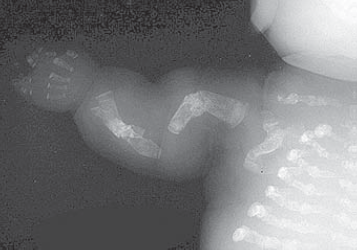

Osteogenesis imperfecta (OI)

20 May

2022/05/20 اقرأ المزيد